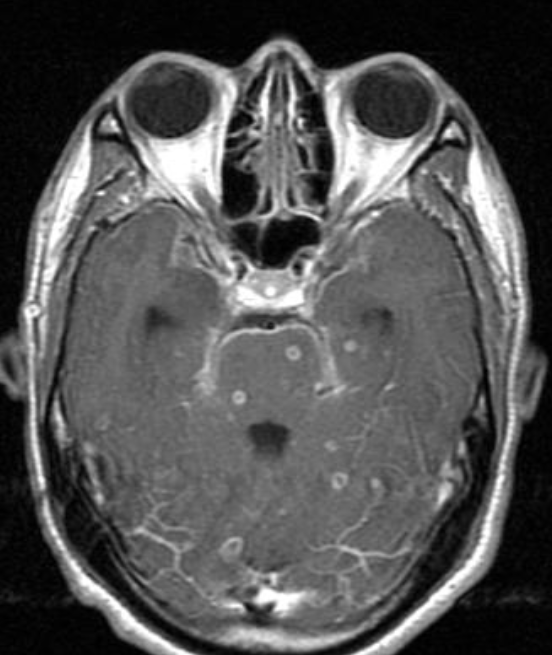

A. Give the name of the pattern of contrast enhancement of the lesion in the given image

- Axial T1 MRI post contrast.

- Multiple ring enhancing lesions

B. Give ONE cause for the pattern of contrast enhancement shown in the given image Tuberculomas ++ Chronic cough / Pulmonary TB